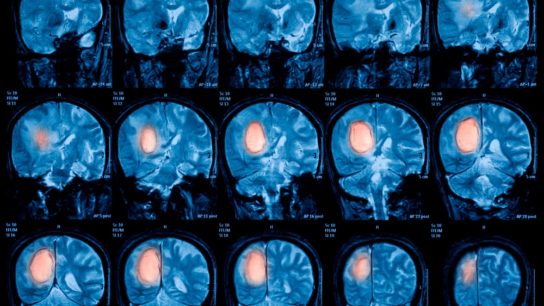

Researchers aimed to compare lobectomy vs other management strategies for glioblastoma in terms of overall and progression-free survival.